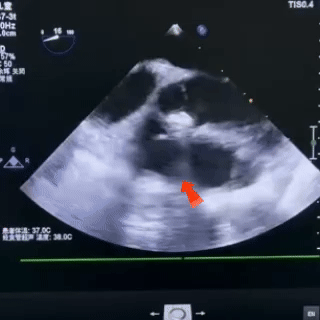

释放后观察

封堵器形态稳固

无残余分流,封堵成功